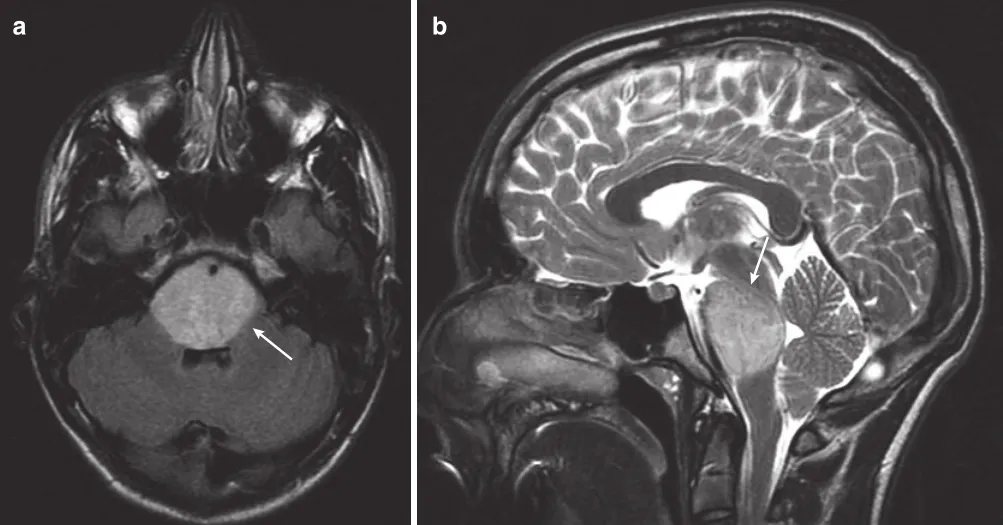

3.诊断方法:DIPG的诊断常常通过MRI进行。通常,脑桥弥性扩大,占脑干该区域的50-75%或更多。可能有外生成分,尤其是腹侧。增强后可能会有强化,但通常是斑片状的,合并脑桥弥漫性肿胀。有时,基底动脉可能完全被肿瘤覆盖(图3)。其他MR序列和技术已用于DIPG,包括显示较低的平均总胆碱浓度的磁共振波谱成像(MRS)和弥散张量成像(DTI),但这些在预测病变的神经病理学特点以及结局方面并未被证明是可靠的。

图:一名14岁男孩的MRI扫描,他有短暂的复视、共济失调和左侧面瘫。(a)轴向FLAIR MRI显示高信号占据整个脑桥(箭头)。(b)矢状T2 MRI显示DIPG使脑桥范围受累(箭头)